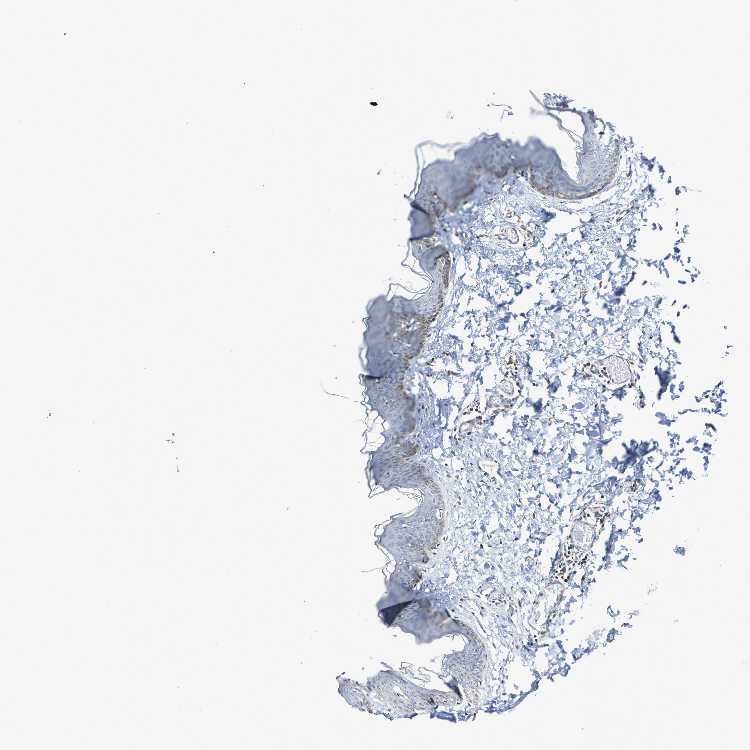

SKIN 2 - Antibody stainingi

Antibody staining in the annotated cell types in the current human tissue is reported as not detected, low, medium, or high, based on conventional immunohistochemistry profiling in selected tissues. This score is based on the combination of the staining intensity and fraction of stained cells.

Each image is clickable and will lead to virtual microscopy that enables deeper exploration of all samples and also displays staining intensity scores, fraction scores and subcellular localization as well as patient and tissue information for each sample.

Antibody HPA007615

Epidermal cells High